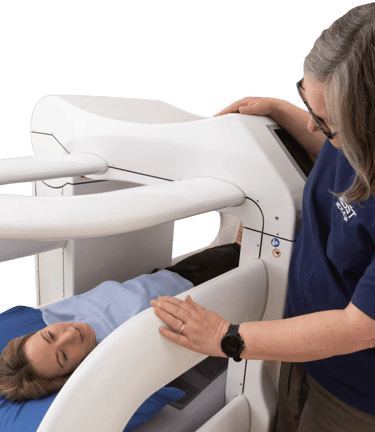

MBST Therapy Advanced Non-Surgical Solution for Joint & Spine Pain

MBST is an innovative German technology that uses therapeutic magnetic resonance to stimulate cell regeneration, repair cartilage, and relieve chronic pain without surgery, injections, or radiation.

Advanced medical technology focused on cellular repair

When pain, stiffness, or injury disrupt your life, real relief should target the source not just cover up the symptoms. MBST offers a different path. By acting directly on the cells where damage begins, it aims to ease pain, reduce inflammation, and improve mobility for people dealing with musculoskeletal issues, chronic discomfort, or long-term conditions.

MBST uses precise magnetic resonance signals to create conditions that support healthy cell activity and natural repair. When cells operate the way they’re meant to, they can better restore balance, regenerate tissue, relieve discomfort, and reduce inflammation.